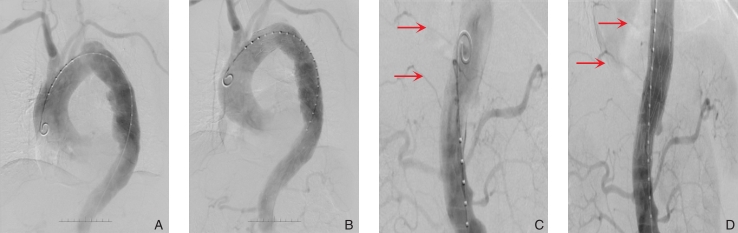

图3 术中情况 A-B:支架置入前后DSA可见胸主动脉多发夹层破口修复;C-D:支架置入后DSA主动脉夹层破口隔绝完全,打孔段肋间动脉显影(红色箭头所示)Fig.3 Intraoperative data A-B: DSA showing multiple intimal tears of the aorta before stenting and complete repair after stenting; C-D: DSA showing the completely occluded tears of the aorta and display of the intercostal branches in the perforation section (indicated by the red arrow)